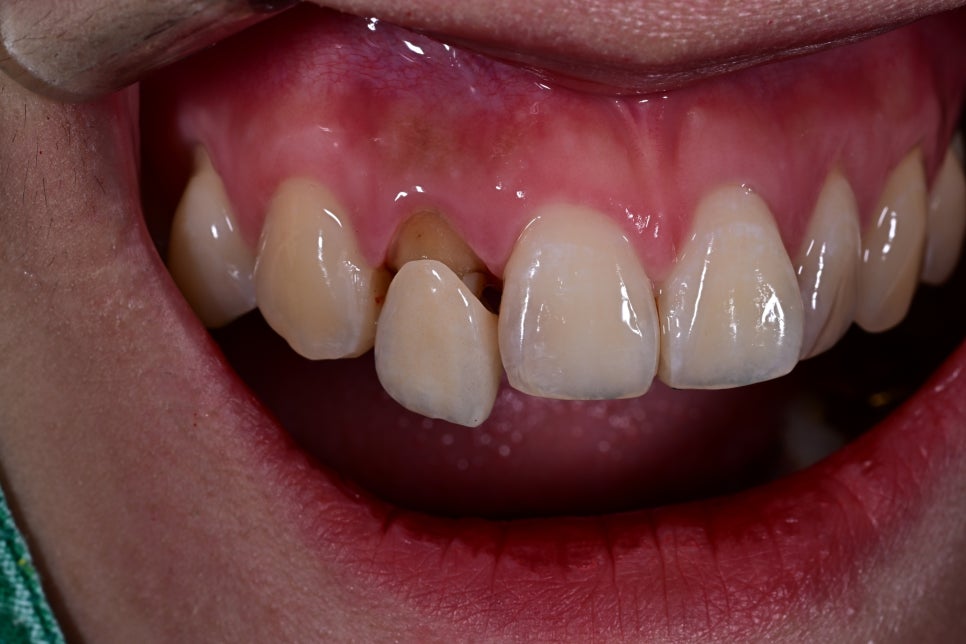

This patient was a 27-year-old woman who visited us because of aesthetic issues with an upper front tooth crown treated about 10 years ago.

A black line visible at the gums

A color difference from the surrounding teeth

An unnatural look in the front teeth

As time passes, upper front tooth crowns can look different from the original result as the gums recede or the internal structure changes. In such cases, rather than simple maintenance, it is necessary to improve them naturally through retreatment.